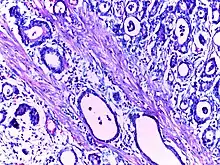

![]() | Adenocarcinoma stomach | Micrograph of carcinoma stomach. The glands are seen infiltrating the muscle layer. The neoplastic cells are arranged in cords and in glandular pattern. The cells show dysplastic features. Signet rings with nucleus pushed to the periphery are seen in some types of adenocarcinoma. | Category: Histopathology of adenocarcinoma stomach | Adenocarcinoma of stomach |